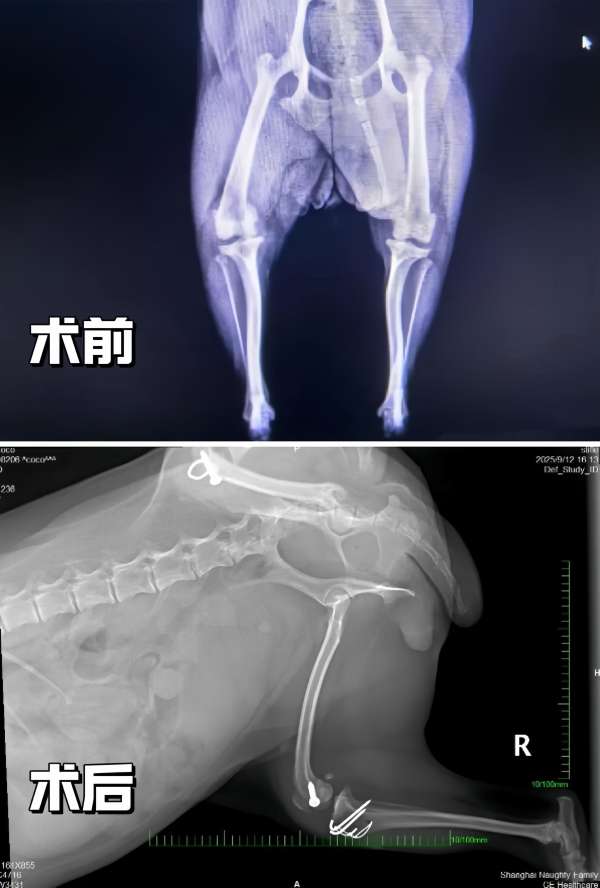

心脏彩超显示Coco存在粘液瘤性二尖瓣疾病(ACVIM B1期)和轻度二尖瓣反流,这一发现为手术麻醉风险评估提供了关键依据。影像学检查进一步确认了双侧髌骨脱位伴关节磨损,关节炎,左侧胫骨和股骨存在畸形。凌凤俊医生解释:“Coco的骨骼畸形是髌骨脱位反复发作的根本原因。传统手术需截骨矫正,创伤大、恢复慢。我们决定采用微创技术,以生物力学原理为核心进行髌骨复位,最大限度减少组织损伤。”

在充分的术前准备与主人信任的支持下,凌凤俊医生先后为Coco顺利完成左、右双侧髌骨修复手术。手术创口小、未进行大规模截骨,Coco术后精神状态与食欲良好,恢复平稳。为免爱犬长途奔波,主人选择留沪直至完成两次手术。目前Coco已顺利出院,步态显著改善,未出现感染及其他并发症。